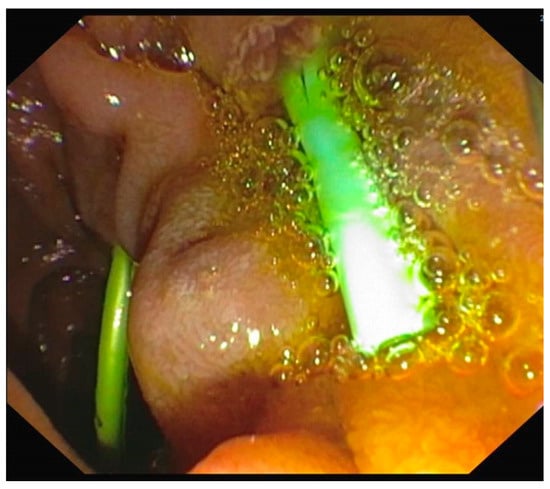

- EUS is a valuable tool for diagnosing pancreas divisum, a common congenital anomaly of the pancreatic duct. Several studies have evaluated its diagnostic yield, demonstrating a sensitivity ranging from 51% to 95% and a high diagnostic accuracy of 97% [40]. MRCP’s sensitivity for comparison with EUS in detecting PD has been reported between 44% and 60%. EUS is particularly effective in identifying pancreas divisum structural features, such as the dorsal pancreatic duct draining into the minor papilla without communication with Wirsung’s duct. This is when the ventral and dorsal ducts fail to fuse during embryogenesis and dominant drainage occurs via the minor papilla (Figure 1).

- Three endosonographic criteria have been suggested for the diagnosis of pancreas divisum with endoscopic ultrasound: (a) Inability to follow the main pancreatic duct from the major ampulla to the pancreas body; (b) Inability to follow the main PD from the hypoechoic ventral pancreas to the hyperechoic dorsal pancreas [40]; (c) The presence of the Stack sign as a possibility of pancreas divisum. The Stack sign is visualized better by positioning the radial echoendoscope (or by linear echoendoscope, reverse Stack sign) in the long scope position with the transducer in the duodenal bulb. When the balloon is inflated and advanced snugly into the apex of the bulb, the bile duct (closest to the transducer) and the pancreatic duct can be seen running in parallel through the pancreatic head [26,41]. Performing EUS, the Stack sign refers to the parallel alignment of three tubular structures seen in the region of the pancreatic head: common bile duct (CBD), ventral pancreatic duct (Wirsung’s duct), and dorsal pancreatic duct (Santorini’s duct). In pancreas divisum (positive Stack sign): the ventral and dorsal pancreatic ducts remain separate and on EUS, three parallel, stacked tubular structures are evident: (a) the CBD (most anterior); (b) the ventral pancreatic duct (Wirsung); (c) the dorsal pancreatic duct (Santorini) (most posterior). This triple-duct alignment is indicative of non-fusion and suggests pancreas divisum.